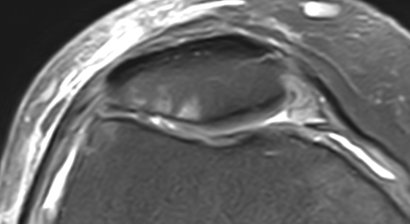

Verletzungen der Rotatorenmanschette

Als Rotatorenmanschette wird jene Muskelgruppe bezeichnet, welche sich zwischen dem Schulterblatt (lat.: Scapula) und dem Oberarmkopf (lat.: Caput humeri) erstreckt und wie eine Muskelhaube den Großteil des Oberarmkopfes umschließt. Eine intakte Rotatorenmanschette gewährleistet durch das funktionel...